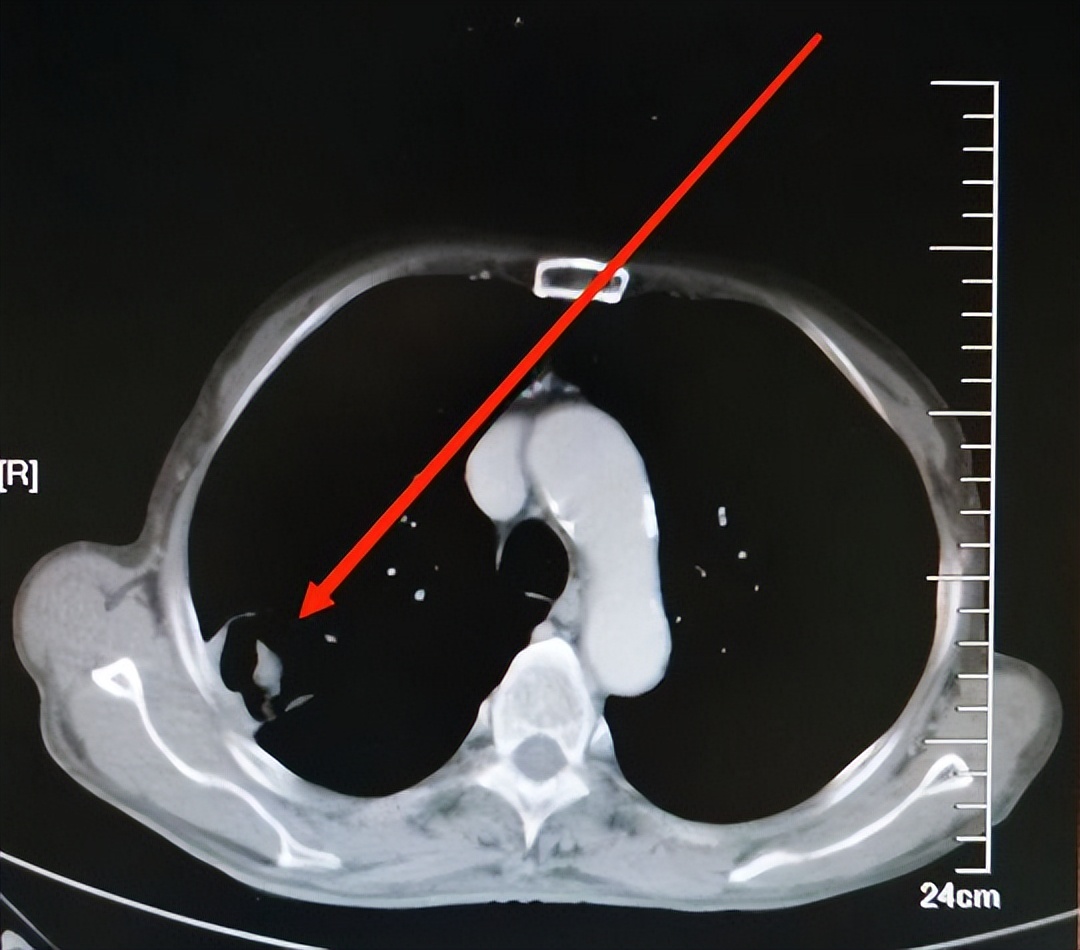

使用安罗替尼单药治疗后,患者无特殊不适,未见明显不良反应。在应用安罗替尼的过程中,患者依从性良好,能够遵医嘱定期复查,最终结果也令人惊喜:四个周期后复查,肺癌病灶明显缩小(见图2)。

图片来源 :讲述者提供